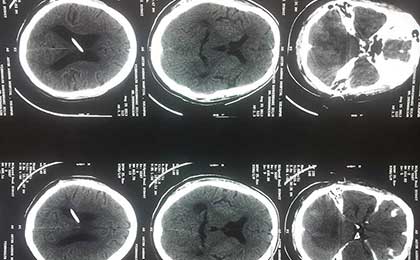

Obstuctive Hydrocephalus

Obstructive Hydrocephalus 2 Pre Op Mri